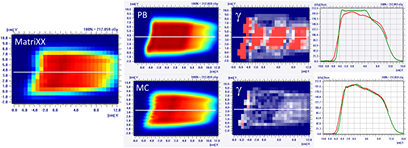

Standard image High-resolution imageThe MatriXX measurement of the configuration represented in figure 4, confirmed what was expected from the MC recalculation: the PB dose profile was higher compared to the measurements and the γ passing rate of the dose distribution estimated on the MatriXX was 57.6%. The MC recalculation is much closer to the experimental data and had a gamma passing rate of 97.8% (see figure 5 and table 1).

Figure 5. Dose distribution and γ analysis comparison between the MatriXX measurement and the PB or MC dose engine in a transversal plane for the 1/6 head phantom with a gantry angle of 70° and snout position of 42 cm. The white lines represent the dose profiles' extraction plans, the red lines are the measured data profile while the green lines represent the calculated dose distribution. The red region in the γ graph represents the area with γ > 1.

Table 1 reports the PB and MC gamma passing rates for all the configurations of the gantry angle and snout position simulated on the most superficial slab of the head phantom (i.e. 1/6). It is interesting to note that also in the case of small air gaps (i.e. RS 20 cm from the isocenter) the γ passing rate of the PB algorithm could be <95%.